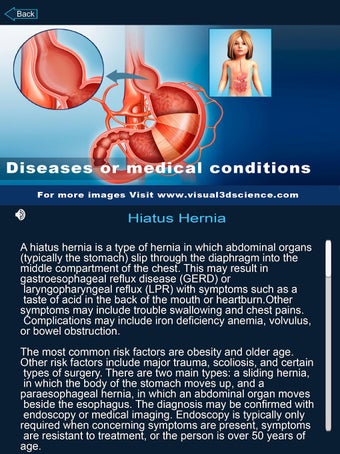

Je kunt alle informatie over de organen krijgen, inclusief hun locatie, hun functie en hoe ze eruitzien.